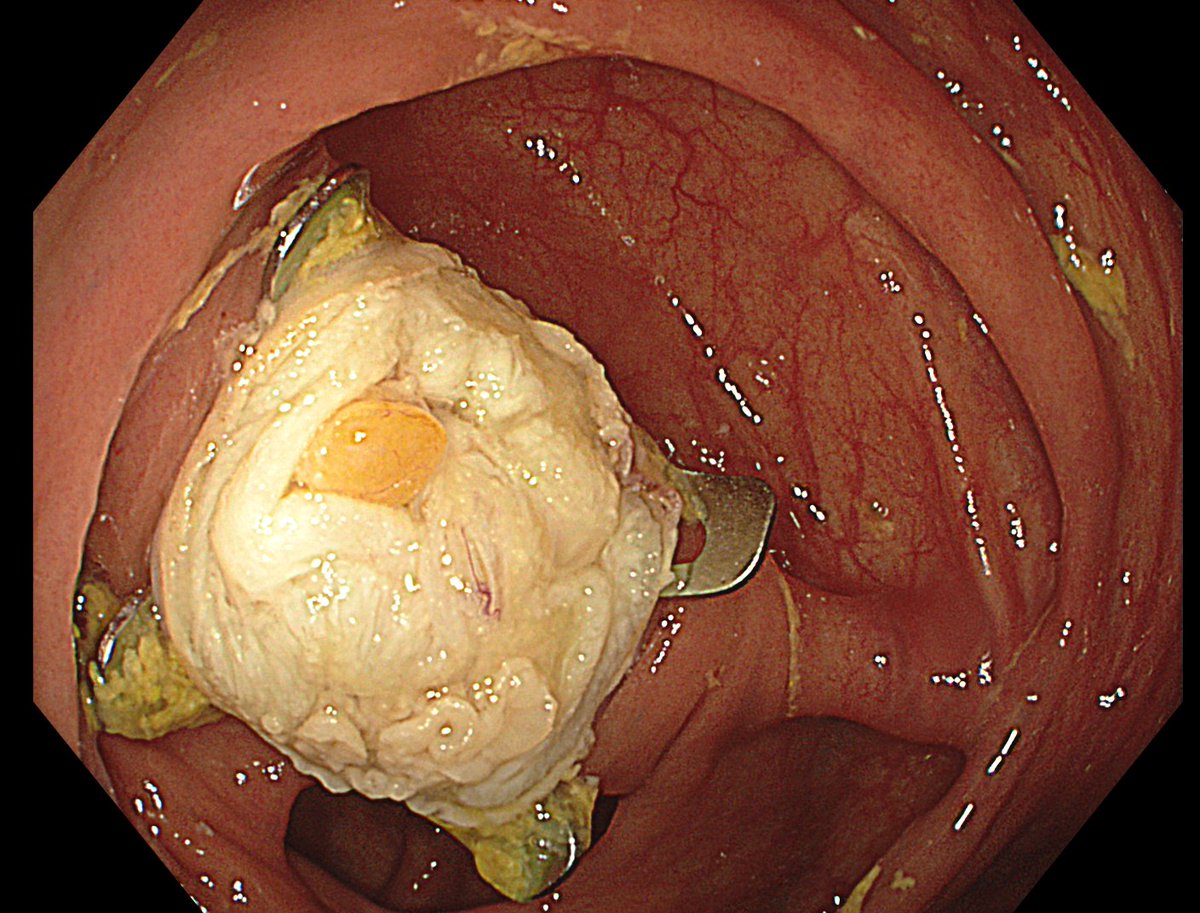

1. Antrum, low grade dysplasia. Removed via ESD. Specimen 43x32mm / dysplasia 20x13mm. R0